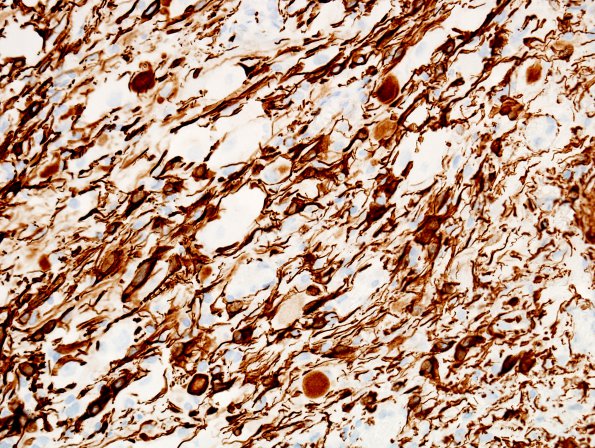

14F Ganglioglioma (Case 14) GFAP 5

Spindled glial cells stain strongly for GFAP (GFAP IHC)